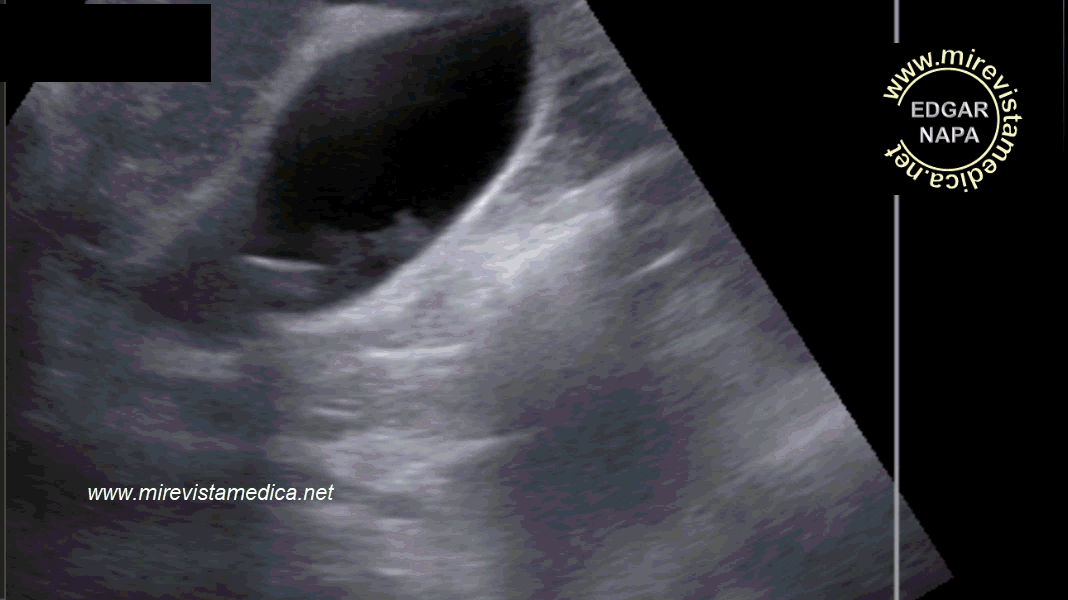

Hallazgos por ultrasonido (US_) :

- imagen hiperecogénica, movil, de márgenes circunscritos que deja sombra acústica posterior (litiasis).

- Signo de Murphy ecográfico. Pain and tenderness with transducer pressure directly over gallbladder.

- Engrosamiento de pared vesicular (se le denomina así cuando es > 3 mm). Hazy delineation of GB wall with echogenic pericholecystic fat.